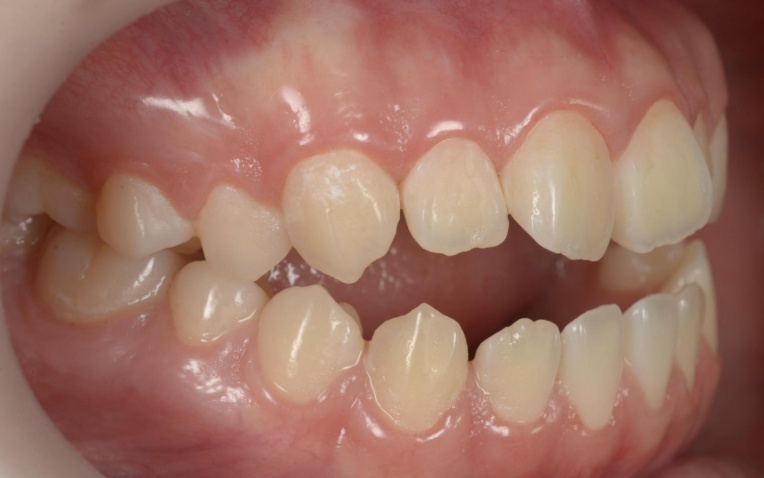

「前歯が噛み合わないので治したい」とご相談いただきました。 |

拝見したところ、重度の開咬(かいこう)が認められました。 |